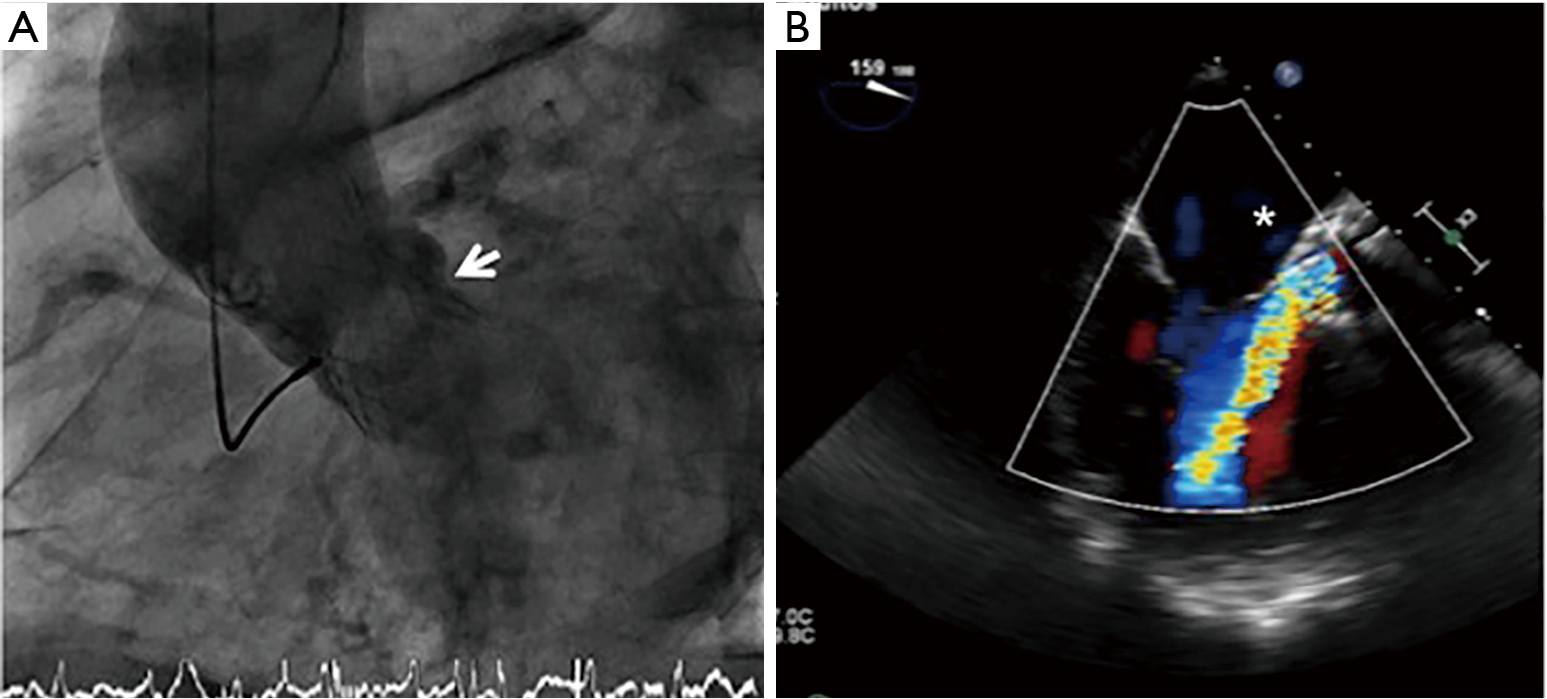

Steps In Paravalvular Leak Closure Echographic Perspective A 3d Echo Download Scientific Diagram Percutaneous closure of paravalvular leak after transcatheter valve implantation in mitral annular calcification by guillaume leurent et al.